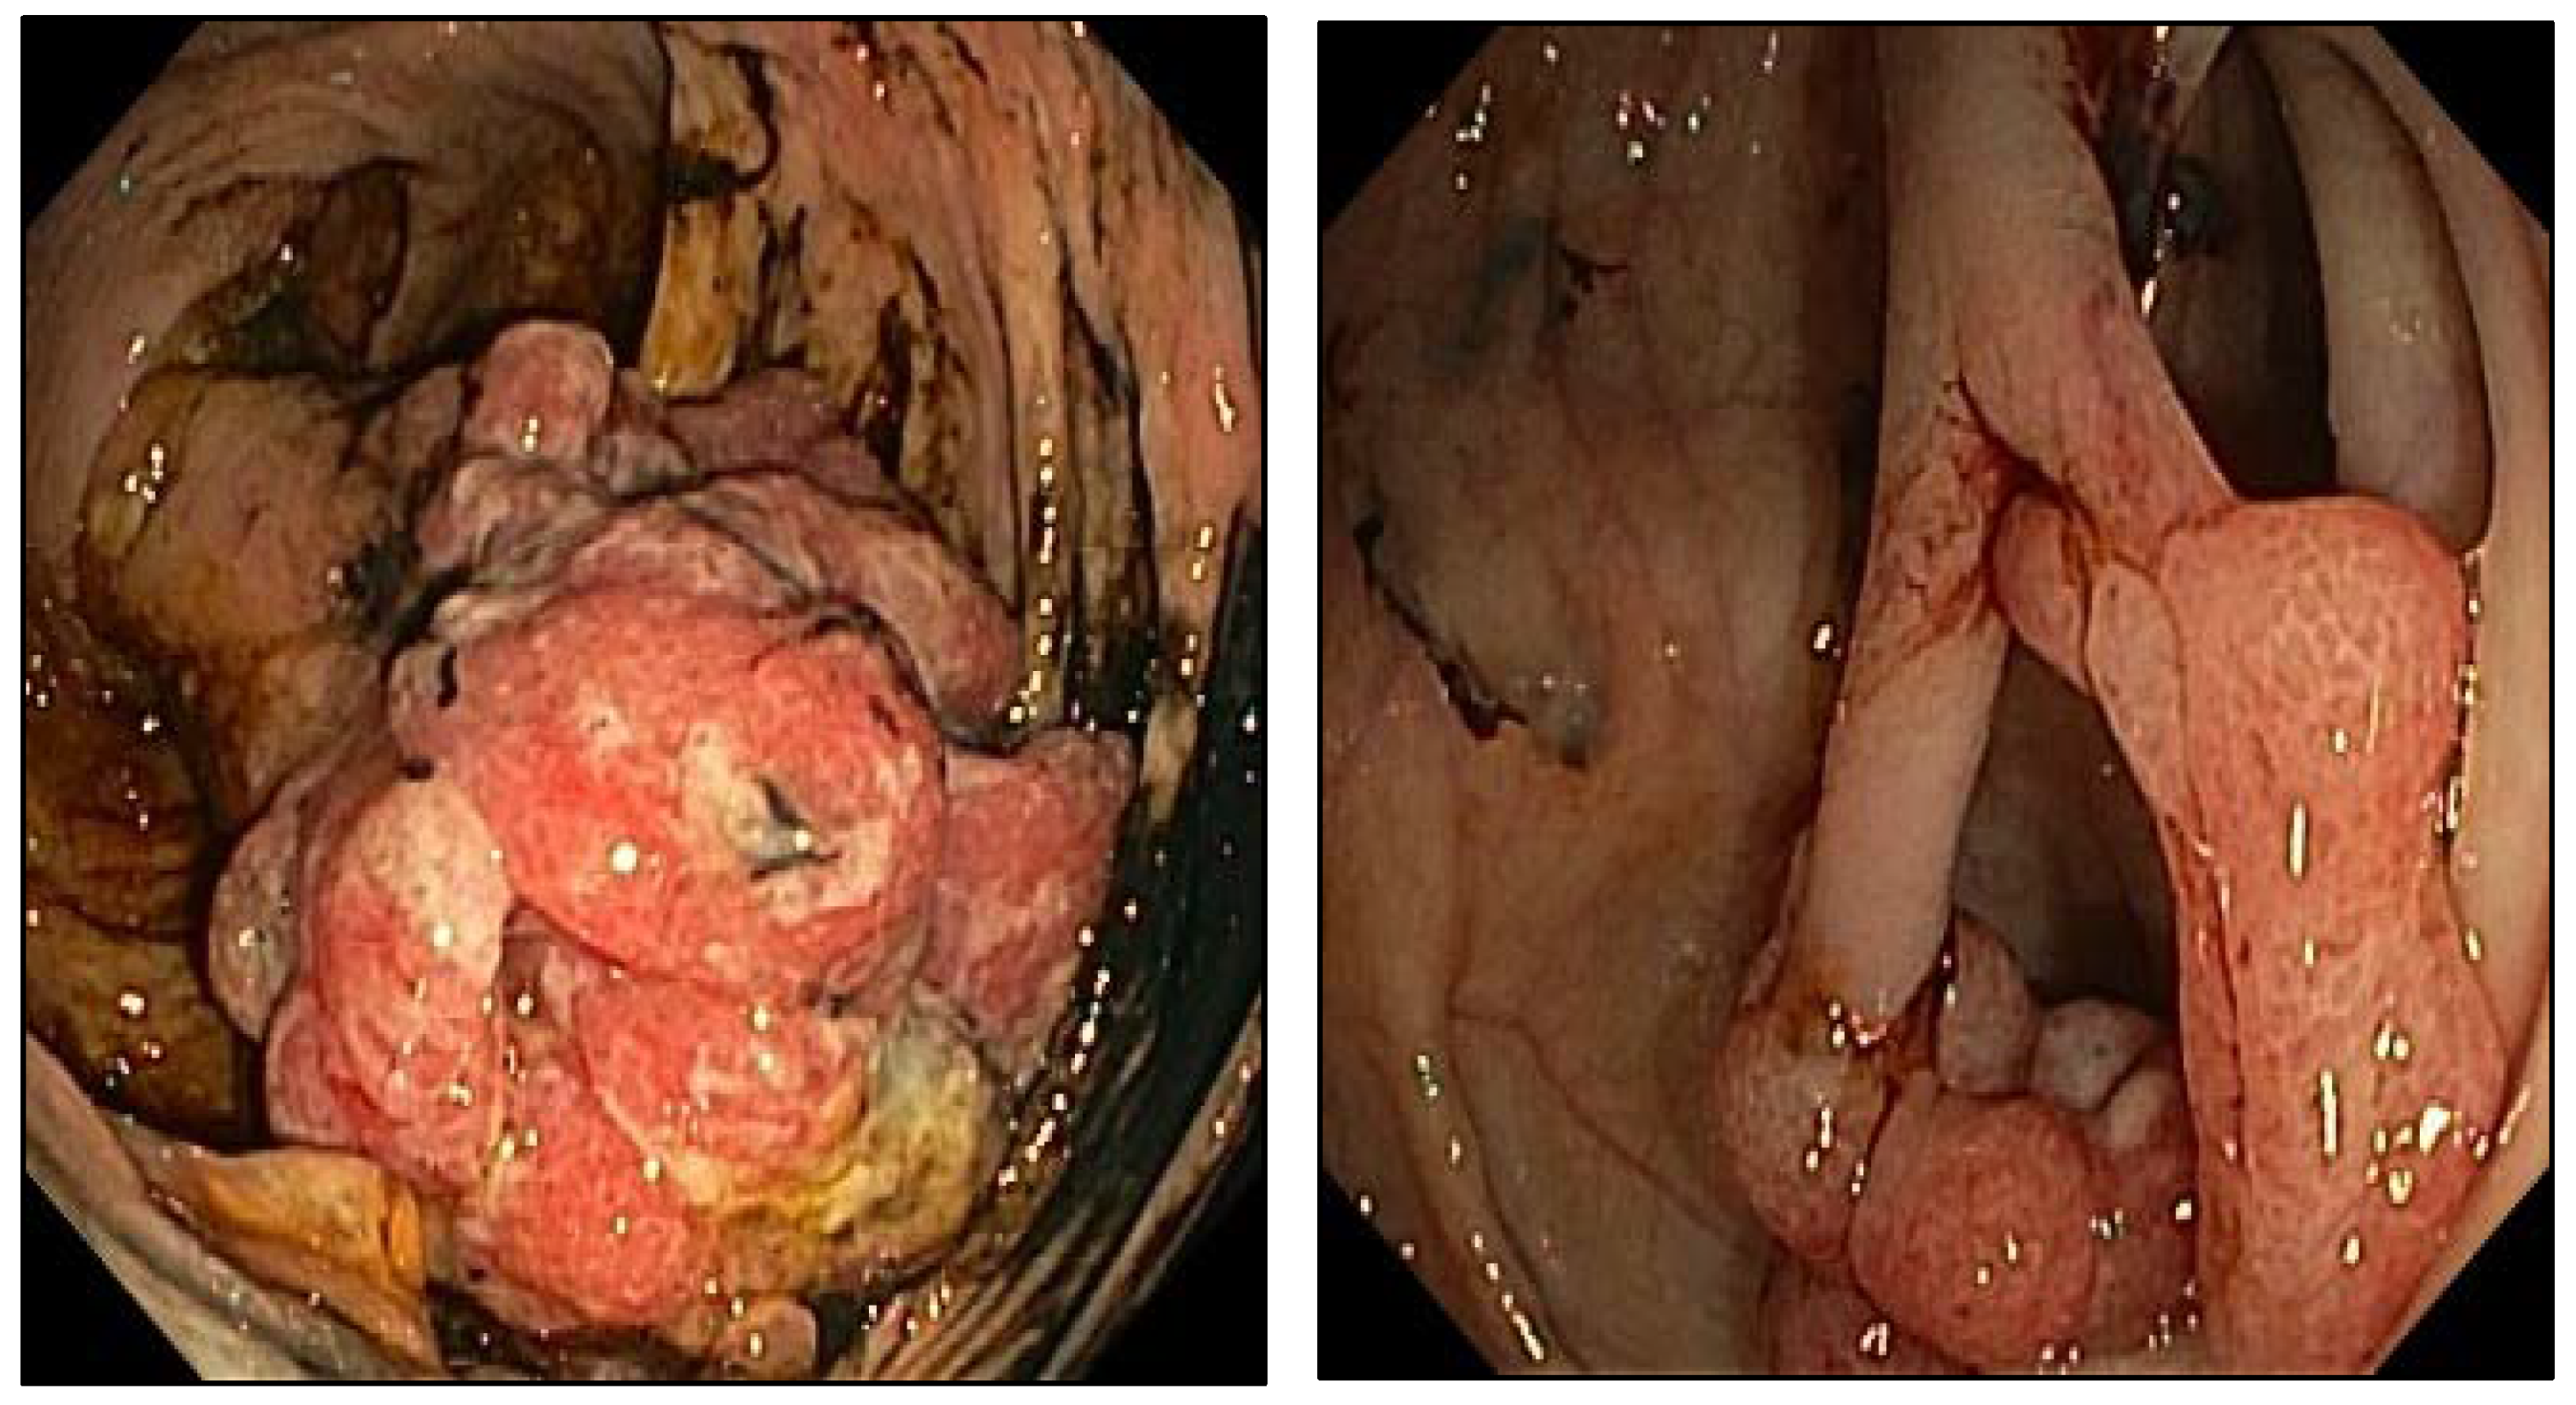

2. Case Presentation